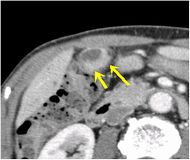

CT画像

胆石症の診断には血液検査、超音波検査、CT検査が有用です。